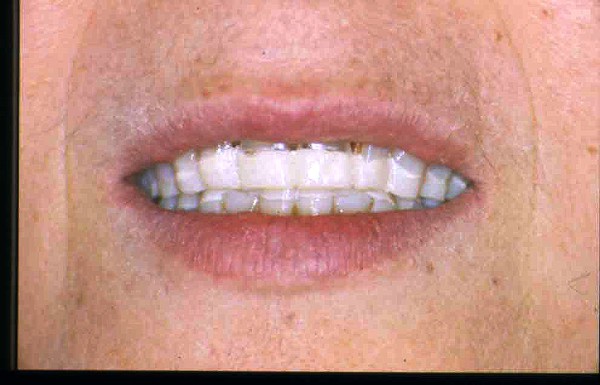

APRECIACIONES DIAGNÓSTICAS EN BASE A LA APERTURA MENTAL DEL CLÍNICO FRENTE A LO QUE EL PACIENTE PROPONE EN MUCHAS OCASIONES , LA DEMANDA DE LOS PACIENTES NOS INCLINAN A FOCALIZAR NUESTRA ATENCIÓN EN LAS PIEZAS DE LAS CUALES EL ENFERMO SE QUEJA. PACIENTE SEXO FEMENINO, 55 AÑOS, SE PRESENTA A LA CONSULTA DERIVADA POR COMPAÑERO GENERALISTA, QUIEN LLEVA MESES PROCEDIENDO A LA «DESINFECCIÓN» DE UN PRIMER PREMOLAR IZQUIERDO, EL QUE SE PRESENTA ABIERTO EN SU CONDUCTO EN EL AFÁN DE PERMITIR EL ESCAPE DE GASES DE UNA GANGRENA PULPAR. A LA INSPECCIÓN CLÍNICA SE OBSERVAN FACETAS PARAFUNCIONALES DE TERCER GRADO , ASINTOMÁTICAS, CON EVIDENTES DIFICULTADES MASTICATORIAS Y ESTÉTICAS , FALTA TOTAL DE SUS MOLARES INFERIORES, Y ADELANTAMIENTO PRONUNCIADO DE SU MANDIBULA, LA QUE CUESTA MANIPULAR DEBIDO A LA SITUACIÓN DE ESPASMO DE CASI TODA SU MUSCULATURA GNATICA. SE ESTUDIA EL CASO RADIOLOGICAMENTE, Y SE RELAJA EL SISTEMA MEDIANTE LAM. DE LONG REALIZANDO UN MONTAJE EN LA ORC OBTENIDA. NO SATISFECHOS CON EL RESULTADO, CONFECCIONAMOS UN JIG DE LUCIA, EL QUE DEJAMOS EN BOCA TODA UNA NOCHE, AL CABO DE LA CUAL REALIZAMOS UN NUEVO REGISTRO REALIZAMOS UN ENCERADO RÁPIDO DEL CASO, Y CONFECCIONAMOS UNA ESTRUCTURA OCLUSAL PLASTICA, QUE ADEMÁS REPONGA EL ASPECTO ESTÉTICO PERDIDO (FÉRULA DE RELAJACIÓN DE COMPONENTE ESTÉTICO), LO QUE PERMITE AL ENFERMO LUEGO DE DOS DÍAS DE USO, NO SOLO CORROBORAR LA COMODIDAD MASTICATORIA Y LA FALTA DE SÍNTOMAS MUSCULARES, SINO TAMBIÉN OBSERVAR APROXIMADAMENTE LA DIFERENCIA ENTRE LA SITUACIÓN INICIAL Y LO QUE PUEDE LOGRARSE MEDIANTE EL TRATAMIENTO. EL PACIENTE ADVIERTE LA MEJORÍA DE LA SITUACIÓN. ACEPTADO POR PARTE DEL MISMO EL TRATAMIENTO SUGERIDO, CREAMOS UN JUEGO COMPLETO DE PROVISORIOS EN BASE AL ENCERADO, Y PROCEDEMOS A TRATAR LA INFRAESTRUCTURA, QUE CONSISTE EN LAS ENDODONCIAS, SUS REFUERZOS A PERNOS DE ORO, LOS ASPECTOS PERIODONTALES DEL CASO, Y DOS IMPLANTES INFERIORES CON TÉCNICA SEMISUMERGIDA ,DE 5 MM DE ANCHO POR 12 DE LONGITUD, CON ANILLO DE ZIRCONIO , A LA ESPERA DE OSTEOINTEGRACIÓN, TRANSCURREN TRES MESES EN EL USO DE UNA NUEVA OCLUSIÓN CONSTITUIDA POR LOS PROVISIONALES, SEGÚN EL ENCERADO, QUE SE REALIZÓ SIGUIENDO LOS CÁNONES DE UNA OCLUSIÓN ORGÁNICA. COMPROBADA LA EFICACIA DE LA NUEVA SITUACIÓN, CON SUS DISCLUSIONES LATERALES Y POSTERO ANTERIORES CORRECTAS, CARECIENDO YA DE SINTOMATOLOGÍA MUSCULAR (SIN MIALGIAS, SIN MIOSITIS, Y CON UN GRADO DE APERTURA DE 4,50 CM), Y SIN SIGNOS EVIDENTES DE DESGASTE SOBRE EL MATERIAL DE LOS PROVISORIOS, ES DECIR: VERIFICANDO QUE EL PACIENTE YA NO BRUXA, VERTICALIZANDO EL CICLO MASTICATORIO /OTORGANDO ORC/ DIMENSIÓN VERTICAL /PROTEGIENDO A LAS PIEZAS `POSTERIORES DE IMPACTOS LATERALES RECIEN ENTONCES , MONTAMOS EN ARTICULADOR SEMI AJUSTABLE LOS MODELOS DE TRABAJO DEFINITIVOS. CONFECCIONAMOS ENTONCES LAS COFIAS INFRA PORCELANA, EN PORCELANA DE ALTA DENSIDAD EN EL SECTOR ANTERIOR Y EN ORO GALVÁNICO PARA EL SECTOR POSTERIOR PARA LUEGO COMPLETAR LA GUIA ANTERIOR , VERIFICANDO LA ALTURA DE LOS INFERIORES RESPECTO DEL LABIO INFERIOR Y CORROBORANDO LOS PUNTOS DE CONTACTOS INTER CANINOS, QUE CENTRALIZAN LA MANDIBULA Y VERTICALIZAN EL CICLO MASTICATORIO Y LAS DISCLUSIONES CANINAS QUE OTORGARÁN PROTECCIÓN A LOS SECTORES POSTERIORES. POSTERIORMENTE CHEQUEAMOS LA DISCLUSIÓN EN PROPULSIVA DE LA GUIA ANTERIOR YA TERMINADA. FIG38 FIG39 UNA VEZ OBTENIDO UN COMANDO ANTERIOR EFECTIVO, COMO LO ES LA GUIA ANTERIOR CON TODOS SUS COMPONENTES, PROCEDEMOS A REALIZAR LAS TABLAS PREMOLAR / MOLAR DE AMBOS LADOS Y OBSERVAMOS QUE LOS PUNTOS INTEROCLUSALES DE CONTACTO SEAN SUFICIENTES Y CUMPLAN SU OBJETIVO DE OTORGAR ESTABILIDAD MESIO DISTAL Y VESTÍBULO LINGUAL. TRANSCURRIDO UN AÑO DE FINALIZADO EL TRATAMIENTO, REALIZAMOS UN CHEQUEO POST OPERATORIO DEL CASO, EN TODOS LOS PARÁMETROS ANTERIORMENTE MENCIONADOS, Y OBSERVAMOS LA ABSOLUTA ESTABILIDAD DEL MISMO EN TODOS SUS NIVELES Y TEJIDOS.